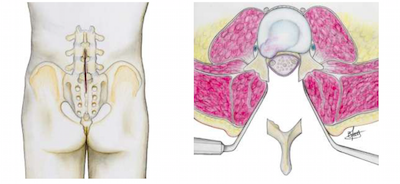

Pour lever la compression des éléments nerveux, il faut supprimer une partie des tissus qui obstruent le canal (formations osseuses, surfaces articulaires, ligaments, voire parties des disques intervertébraux).

• L’intervention se fera sous anesthésie générale. L’anesthésiste vous en précisera les modalités et les risques. La plupart du temps cette intervention se pratique sur le ventre ou en position genou fléchi. Une sonde urinaire est généralement mise en place dès le début de l’anesthésie. Un court examen radiologique, pratiqué sur la table d’opération, permet de localiser la partie du canal rachidien rétrécie et de déterminer précisément l’emplacement de l’incision cutanée.

• L’incision cutanée se fait dans le dos, la longueur de celle ci dépend du nombre d’étages à opérer, de la nécessité de fixer ou non les vertèbres. Une fois les tissus incisés, le chirurgien écarte les muscles du dos de part et d’autre pour avoir accès au canal. Les actes chirurgicaux peuvent ensuite être différents selon le type de sténose. En fonction, du diagnostic, de l’examen clinique et des résultats radiographiques, l’opération va consister à ôter des fragments d’os ou d’articulation, des tissus ligamentaires ou une hernie discale. Chaque cas étant différent, les modalités précises de l’intervention vous seront précisées par votre chirurgien.

stenose chirurgie

Incision cutanée et principe de la laminectomie